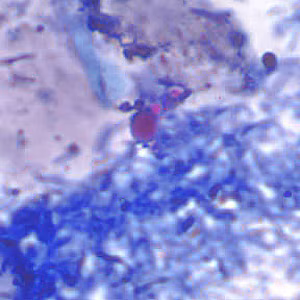

Artifacts in acid-fast stained stool specimens.